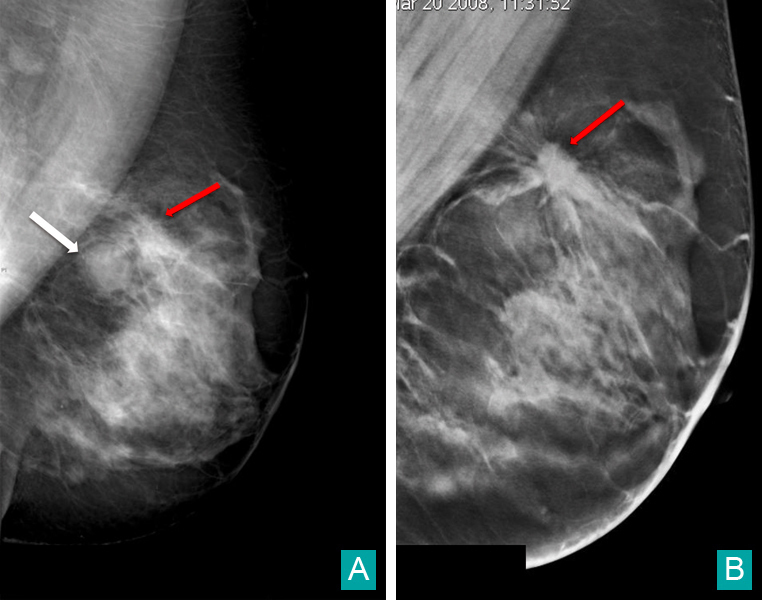

Patiente âgée de 58 ans réalisant une mammographie systématique dans le cadre du dépistage organisé. Le bilan réalisé deux ans auparavant montrait un kyste profond banal du quadrant supéro-externe gauche. Sur l'incidence oblique gauche (fig. A), on retrouve la masse ronde profonde bien circonscrite prépectorale supérieure correspondant au kyste connu (flèche blanche), classée BI-RADS 2. Au-dessus de cette masse (flèche rouge) est apparu un surcroît de densité mal défini dont les contours semblent spiculés. Un cliché complémentaire de tomosynthèse en incidence oblique est réalisé (fig. B) et permet de mettre plus clairement en évidence les spicules de la lésion classée BI-RADS 5. La biopsie a confirmé la malignité.